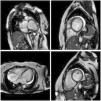

MRI is a high-quality and well-established test for assessing cardiac anatomy and function (Figure 2). It is able to determine cardiac chamber volume and degree of contractility, as well as to diagnose thrombus if present. The most effective analysis of cardiac tissue is by infusion of gadolinium, which can identify and quantify areas of the heart with fibrosis.82,83

Cardiac magnetic resonance imaging showing congestive heart failure/cardiomyopathy of probable inflammatory etiology (Chagas myocarditis), with significant dysfunction and increased biventricular diameters, significantly dilated right atrium and tricuspid regurgitation, dilated left atrium and mitral insufficiency, and pericardial effusion.

Some patients develop malignant arrhythmias without global ventricular systolic dysfunction but with myocardial fibrosis that can be detected by MRI.84,85